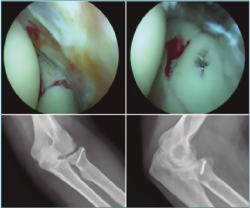

La reducción abierta y la fijación interna es el tratamiento recomendado para las fracturas de tipo III debido a la alta incidencia de inestabilidad asociada con estos grandes fragmentos de fractura. La intervención quirúrgica también se recomienda para cualquier fractura del proceso coronoide que interfiera con el movimiento articular(4). Si hay un alto grado de conminución de la fractura coronoide y no es posible la fijación interna, se indica la colocación de fijación externa para mantener la congruencia de la articulación del codo durante la cicatrización del tejido blando y óseo. Cuando hay presente un gran fragmento de fractura de un proceso coroideo, sin embargo, puede visualizarse y asegurarse de forma efectiva utilizando técnicas artroscópicas. Se puede fijar con AK o bien insertar una guía de ligamento cruzado anterior tibial a través del portal medial anterior y se usa para manipular y reducir anatómicamente el fragmento de la fractura. A continuación, taladramos el olécranon desde fuera hacia la articulación controlado con visión directa hasta atravesar la fractura de la coronoides. Luego, se puede usar distintas técnicas, desde una lazada con sutura de alta resistencia (Figura 7) hasta un pequeño tornillo canulado para asegurar el fragmento de fractura del proceso coronoide y ayudar a restablecer la estabilidad de la articulación(5).

Figura 7. Fractura de coronoides asistida por artroscopia con sistema de lazada.